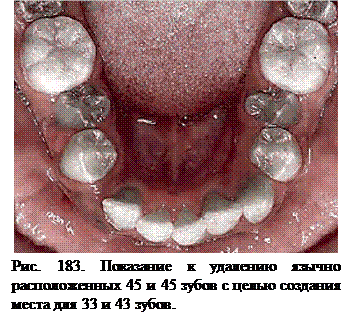

Удаление второго премоляра (одного или двух) проводится значительно Реже, чем первого. Их удаление возможно при: 1) небном, язычном или вестибулярном положении, значительном недостатке или отсутствии для них места в зубном ряду; 2) сочетании удаления первых премоляров на одной челюсти и «выравнивающей экстракции» вторых премоляров - на другой, чаще нижней челюсти, при выраженном тесном расположении нижних резцов; 3) адентии отдельных вторых премоляров ("выравнивающая экстракция" на противоположной челюсти); 3) ретенции вторых премоляров, показаниях к мезиальному перемещению первых постоянных моляров.